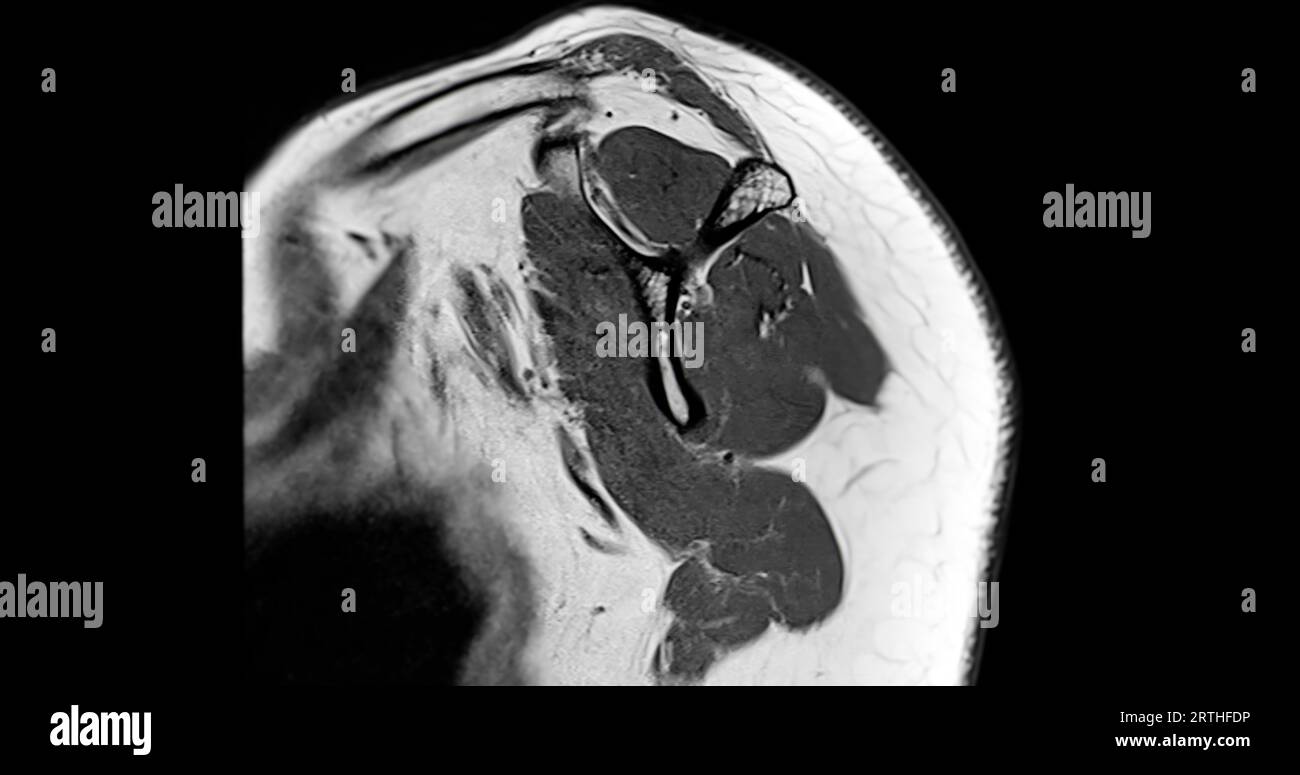

MRI Shoulder Musculoskeletal Imaging

What Can Mri Of Shoulder Detect . magnetic resonance imaging (mri) of the shoulder uses a powerful magnetic field, radio waves and a computer to produce. a shoulder mri is a test that uses a magnetic field to take pictures of your shoulder. The mri allows accurate assessment of. in particular, the images include your muscles, ligaments, and cartilage as well as any other components. magnetic resonance imaging, or mri, uses a magnet to examine the inside of your body, useful for diagnosing shoulder pain and. magnetic resonance imaging (mri) of the shoulder is done to: what can a shoulder mri diagnose? the evaluation of the shoulder, and especially its soft tissue structures, is best done with an mri. Learn more about what it’s for,. A shoulder mri can diagnose tears of the rotator cuff, labrum, and tendons.